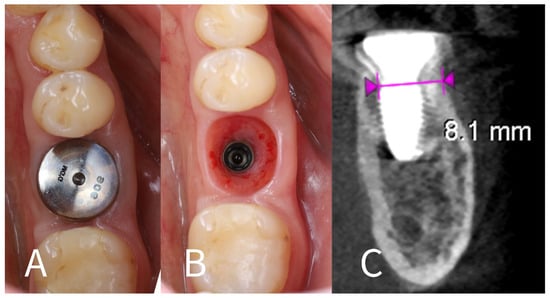

- Implant placement: A dental implant (Megagen Blue Diamond, 4.8 mm diameter × 10 mm length, conical “Deep thread” design) was inserted into the prepared osteotomy. The implant was centered within the socket, with its shoulder positioned roughly 5–6 mm below the level of the surrounding gingival margin (Figure 4). The implant fits snugly between the two buccal shields without exerting undue pressure on them. Primary stability was achieved; the implant had an insertion torque of about 35 N·cm, and verification with a resonance frequency analysis device showed an Implant Stability Quotient (ISQ) exceeding 70. (This high primary stability indicated that the implant was well stabilized in the septal bone despite the immediate placement.)

- Socket sealing with healing cap: The socket orifice was sealed with a large-diameter healing abutment instead of suturing a flap. A wide, 9 mm diameter, and 6 mm height standard healing cap was attached to the implant, which effectively covered the socket opening and conformed to the circumference of the socket (Figure 5). This approach is intended to protect the socket and support the surrounding gingival margins without requiring a flapped closure or graft. No additional bone graft or membrane was placed in the socket; a blood clot was allowed to fill the gaps between the implant and shields [17].

- Immediate post-op imaging: A postoperative CBCT scan was obtained to evaluate the implant position and to measure the alveolar ridge dimensions after implant placement (Figure 6). CBCT confirmed that the implant was accurately centered in the socket.